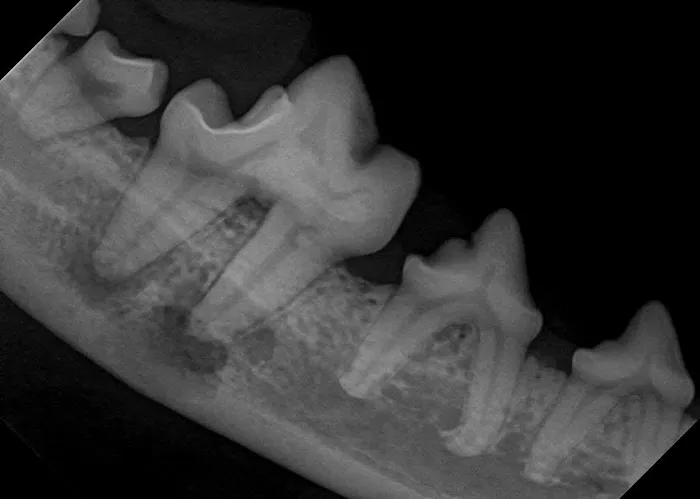

- Diagnostic Imaging and 3D Imaging: Utilizing **Dental Radiographs**, **X-Rays**, **Computed Tomography (CT Scan)**, and Cone Beam Computed Tomography (**CBCT**) for precise diagnosis of hidden disease below the gumline and within the jawbone.